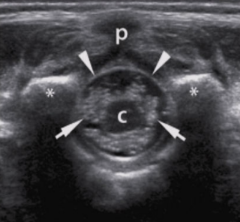

c

hypoechoic spinal cord

arrows

echogenic nerve roots of cauda equina

arrowheads

echogenic dura

*

echogenic vertebral arches

p

spinous process